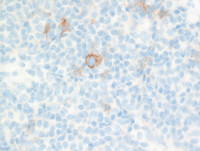

CD20 and CD3 stains

The lesion contains numerous T-cells on CD3 immunostain. However, CD20 immunostain also highlights a fair number of small B cells. The excess of background small B cells is frequently seen in this lymphoproliferative disorder compared to other  T cell lymphoproliferative processes.

PCSMTL-CD20